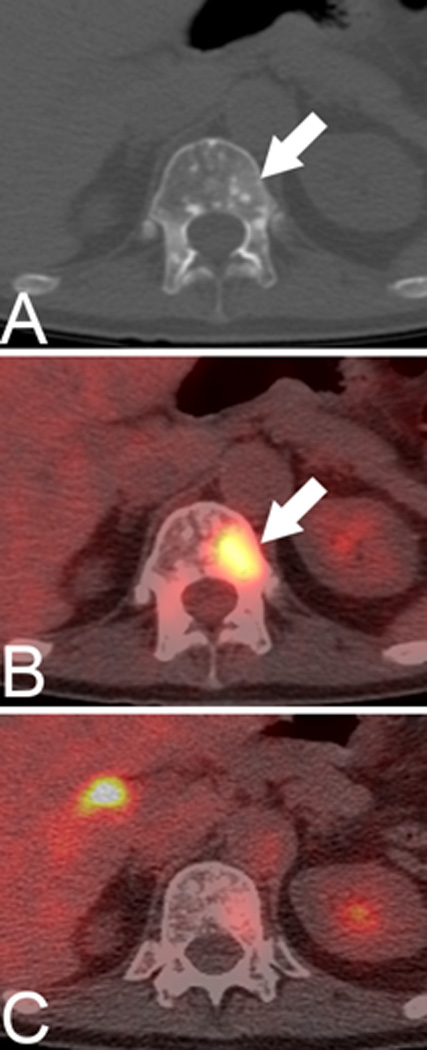

Figure 3.

In vivo imaging of therapy response with 89Zr-7E11 ImmunoPET in xenograft-bearing mice. (A) Representative transverse and coronal 89Zr-7E11 immunoPET images at different time points in a LNCaP xenograft-bearing mouse treated with selective radiation to the right side. Increased uptake of 89Zr-7E11 was observed in the selectively irradiated tumor (right) compared to the control (left). T: Tumor, Li: Liver. The dashed line represents the position of the perpendicularly oriented image. (B) 89Zr-7E11 uptake values (obtained from the PET data as maximum %ID/g) were significantly higher in irradiated than control tumors at 24 h (P=0.0376), 48 h (P=0.0009), 72 h (P=0.0086), 96 h (P=0.01), 120 h (P=0.0075). With permission from Ruggiero A et al. (2012) J Nucl Med 52(8):1608-15